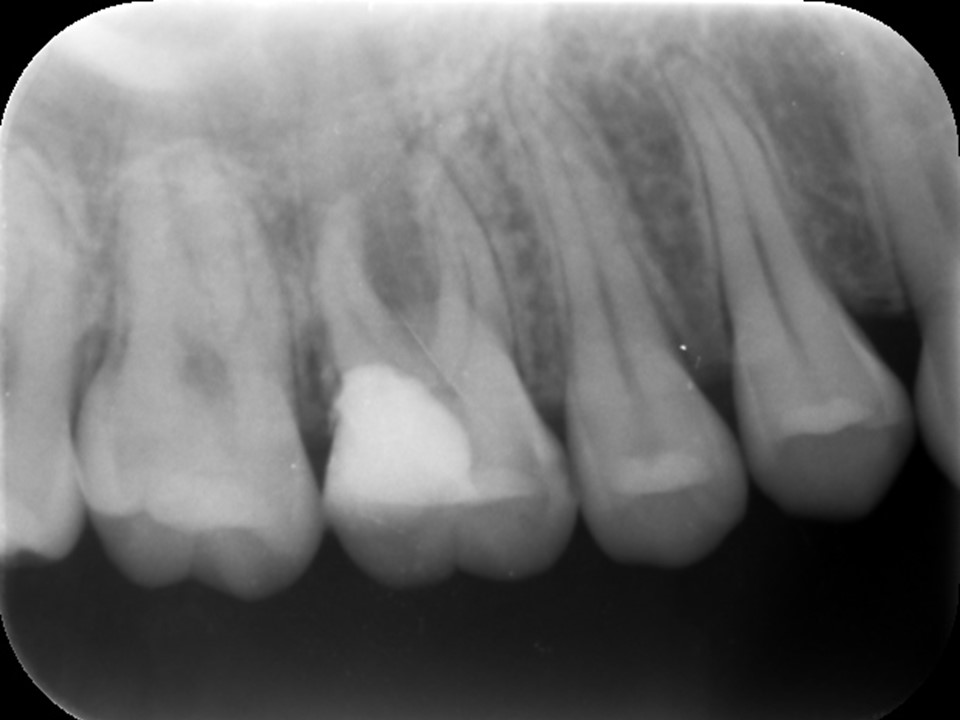

右上の6番の大臼歯に、大きなコンポジットレジン充填がしてありました。レントゲンおよびCT診査を行ったところ、歯髄に達する大きな充填の跡が見られ、根尖部の骨はすでに大きく溶けて吸収しており、炎症は副鼻腔に達していました(下写真)。レントゲンおよびCT画像から、虫歯治療後の歯髄壊死・壊疽から生じた慢性化膿性根尖性歯周炎と診断しました。また、根尖病変に起因する歯性上顎洞を併発していると診断しました。

治療前のレントゲンおよびCT画像です。右上6番には歯髄に達する大きなコンポジットレジン充填がされています。

根尖部の骨は黒く大きく溶け(赤矢印)、ほぼ上顎洞と交通しています。

上顎洞内部は上方までX線不透過性が亢進し(白くなっています)、典型的な上顎洞炎の像を呈しています(黄矢印)。

根管充填後のレントゲン画像です。根尖部までしっかりとお薬が詰まっているのが分かります。根尖病変および歯性上顎洞炎の予後を確認するため3か月ほど経過観察を行います。